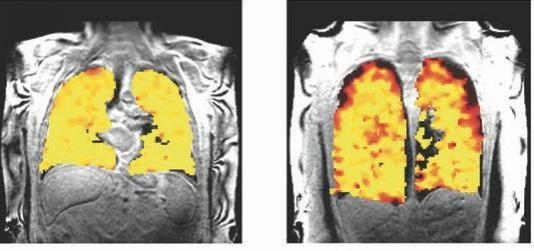

"Our scans show where there is patchy ventilation in patients with lung disease, and show us which parts of the lung improve with treatment," said project lead, Professor Pete Thelwall at Newcastle University.

The new scanning technique allows the team to quantify the degree of improvement in ventilation when patients have a treatment, in this case a widely used inhaler, the bronchodilator, salbutamol. This shows that the imaging methods could be valuable in clinical trials of new treatments of lung disease.